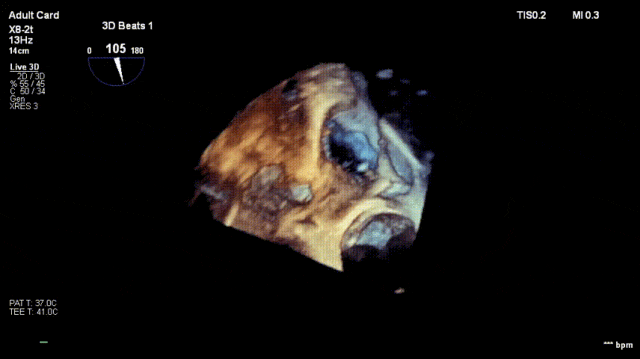

4. The same procedure is performed for the second clip; the clip morphology is stable under ultrasound

Regurgitation assessment: Regurgitation severity reduced from preoperative 5+ to 1+.

Annuloplasty effect: The tricuspid annulus area decreased from 13 cm² preoperatively to 7 cm².